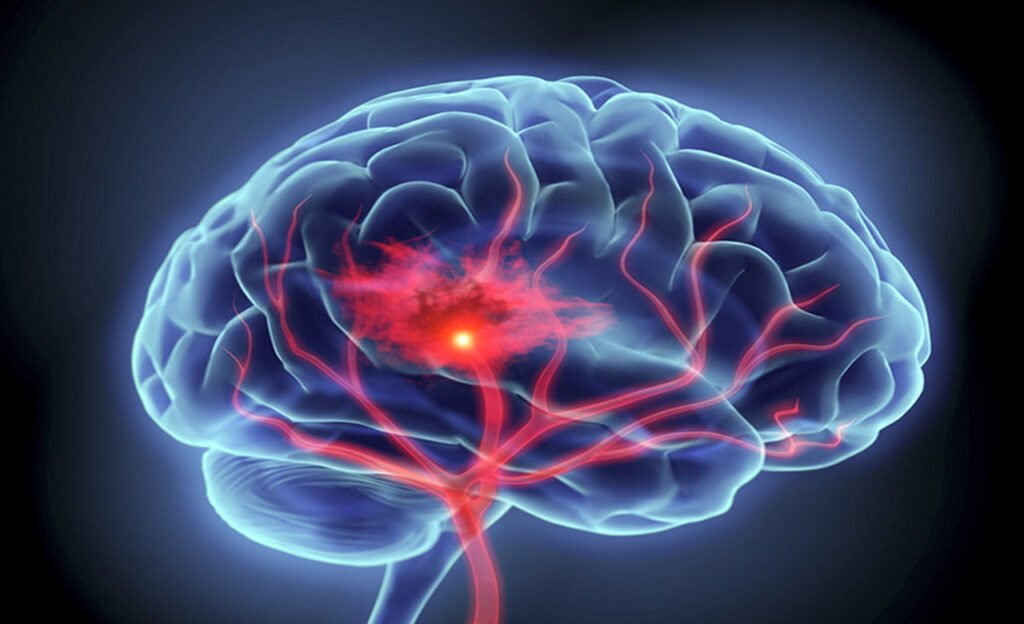

Hemorragia Cerebral

O que é uma hemorragia cerebral? A hemorragia cerebral é o extravasamento de sangue para dentro do tecido cerebral, geralmente de forma abrupta e com potencial […]